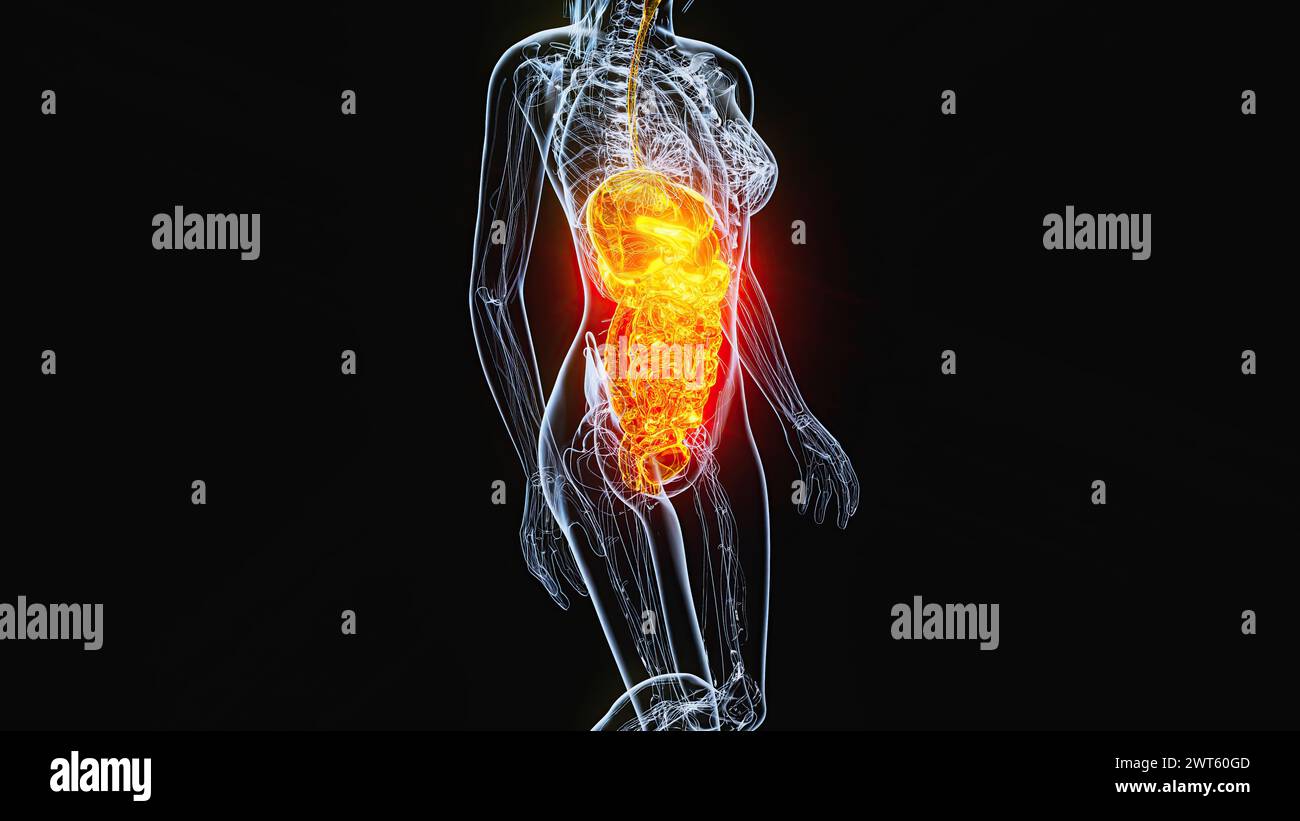

Organes abdominaux et pelviens féminins, illustration. Banque D'Imageshttps://www.alamyimages.fr/image-license-details/?v=1https://www.alamyimages.fr/organes-abdominaux-et-pelviens-feminins-illustration-image600036429.html

Organes abdominaux et pelviens féminins, illustration. Banque D'Imageshttps://www.alamyimages.fr/image-license-details/?v=1https://www.alamyimages.fr/organes-abdominaux-et-pelviens-feminins-illustration-image600036429.htmlRF2WT60GD–Organes abdominaux et pelviens féminins, illustration.